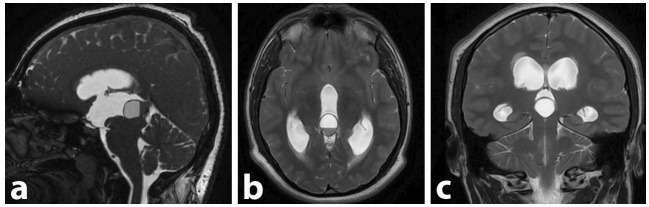

Pineal cysts (PCs) are common findings on (Magnetic resonance Imaging) MRI, often incidental in females and asymptomatic throughout life. Rare complications, like pineal apoplexy with acute hydrocephalus, require differential diagnosis and urgent intervention. We report a 19-year-old male with a progressive headache and visual decline. MRI showed a 2.3 cm pineal cyst with hemorrhagic features (apoplexy) causing hydrocephalus. He underwent endoscopic third ventriculostomy and microsurgical resection, both successful. Postoperatively, symptoms resolved completely. Though often benign, complicated PCs can be life-threatening. This case highlights their management, aiding understanding of etiologies, differential diagnoses, and treatments, enhancing medical knowledge.